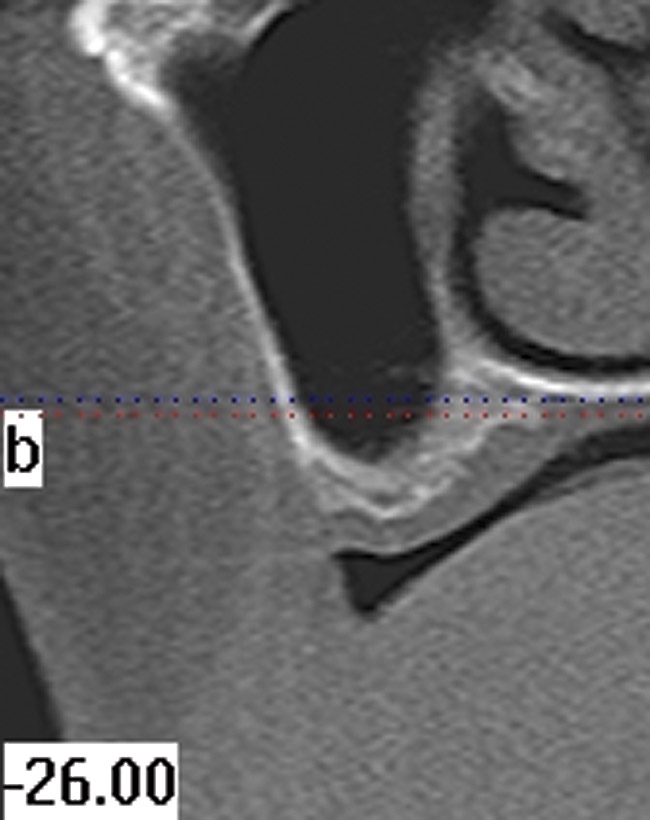

Figure 2  CT scan of the mandibular canal, relative to the expected location of implant placement. Inadequate bone in this region will address modification of the implant used, the need for osseous regeneration first, or in the most severe cases, possible contraindication for implant placement.

Figure 2

Figure 3  CT scan of the mandibular canal, relative to the expected location of implant placement. Inadequate bone in this region will address modification of the implant used, the need for osseous regeneration first, or in the most severe cases, possible contraindication for implant placement.

Figure 3